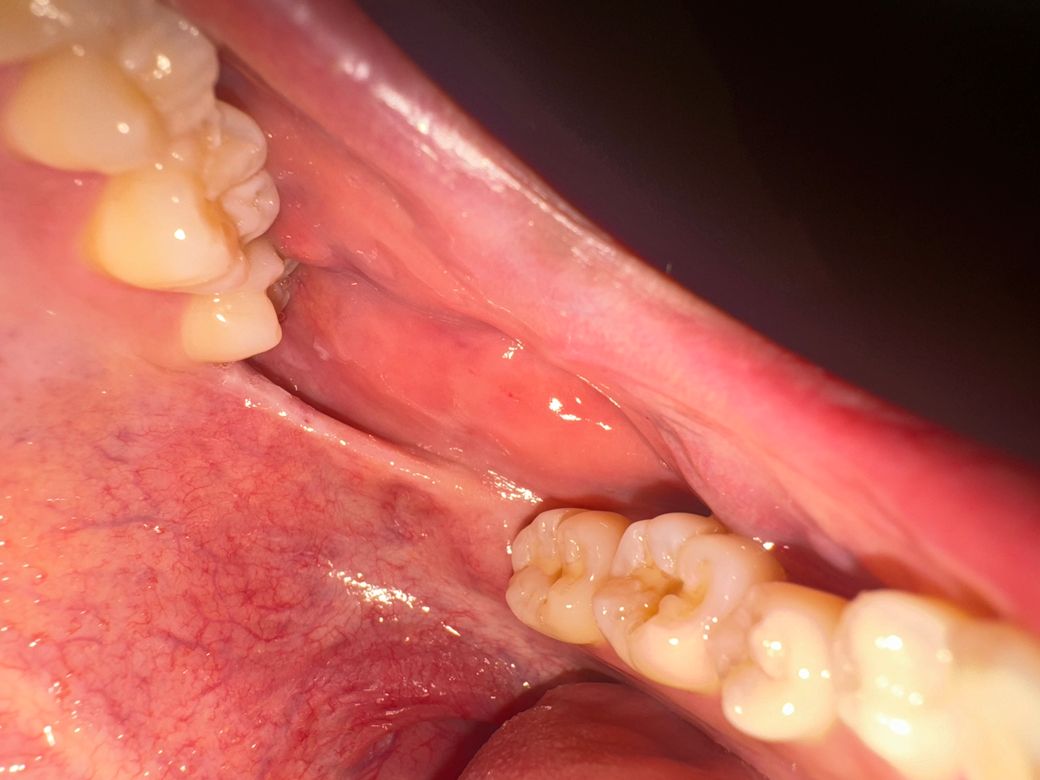

왼쪽 위 사랑니나는 자리에 염증같은게 안사라져요

사진에 보시는것처럼 위사랑니자리위치와 아래사랑니자리 위치 사이 이어져있는 부분이 입을 벌리면 너무 땡겨요 그리고 흰색 뾰루지같은 염증이 생겨있어요. 한 두달정도 됐는데 안사라져서 어제 알보칠을 발랐는데 여전히 남아있네요. 구강암같은 증상일까요? (사진에 보이는 딱 왼쪽 위 자리만 사랑니가 없는데 그 위치만 통증이있네요.) 두달전에 오른쪽 아래 어금니에 충치떼우면서 입을 크게 벌린 적이 있었는데 그 때부터 통증이 생겼습니다.

• 1번 째 사진

• 사진으로 봤을 경우에는 구내염의 가능성이 높아집니다. 구내염은 몸의 면역력이 떨어지게 되어 점막에 염증이 생겼을 때 생기게 됩니다. 결과적으로 몸의 면역력을 올려주는 것이 구내염의 좋은 치료 방법입니다

• 단순 구내염으로 보입니다. 구내염 약 발라주시고 충분히 쉬면 사라질것으로 판단됩니다.

혹시 크기가 계속 커지면 치과 가보시는 게 좋겠습니다.